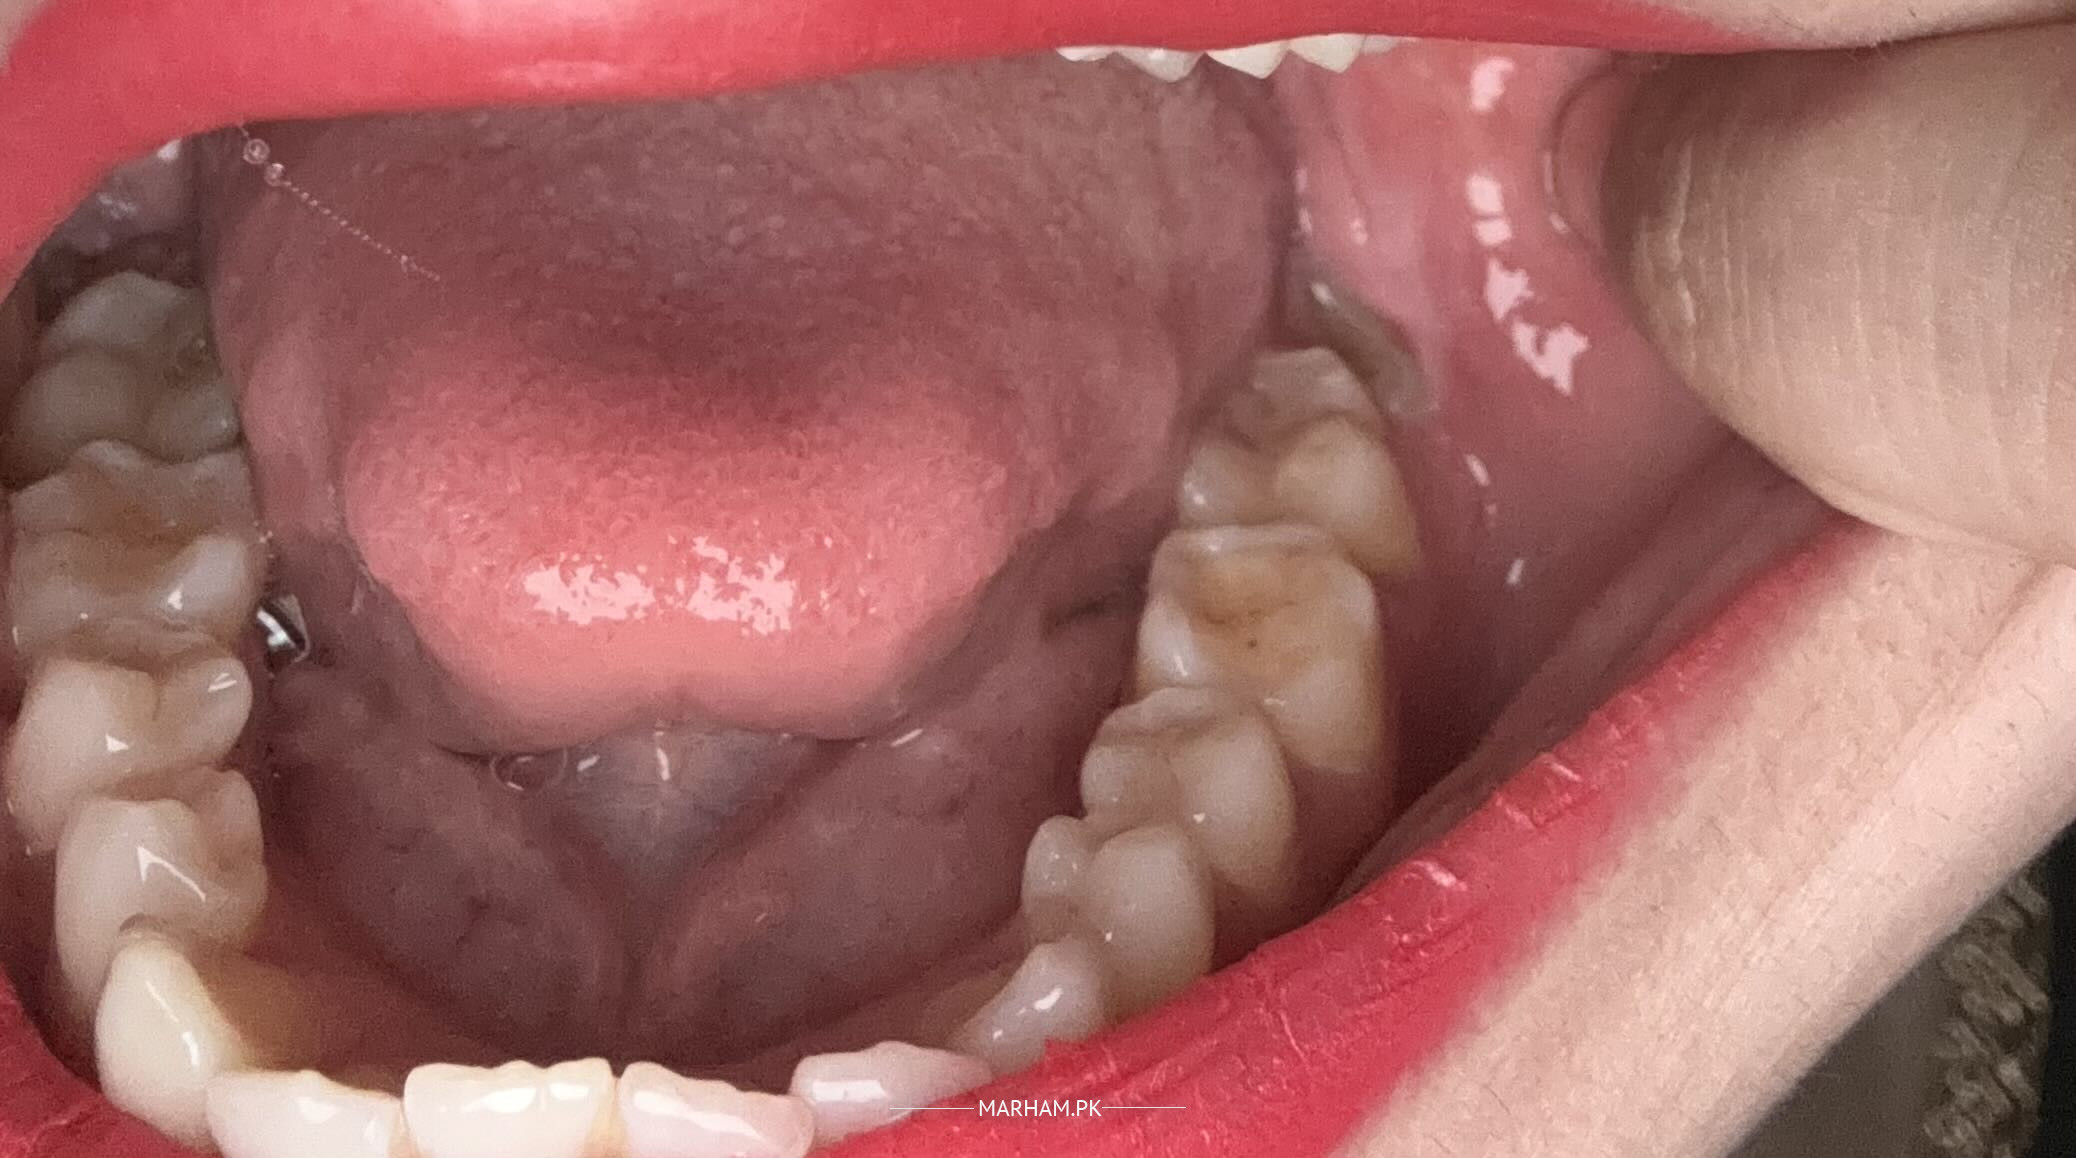

hello i am 26 years female MF 1 year.I took clomid from 2-6 days of my cycle and during that i developed gums swelling(gingivitis) .I am having ferti M injections for day 6,8, is my cycle day 8,i want to ask can i take augmentin for my infection while on these injections? Does it affect ovulation induction?

that redness could be due to hormonal imbalance to whom you might considering gingivitis, well don't worry about it. don't go for augmentin , rinse your mouth enziclor mouth which should be diluted with tap water. 1 cup of mouthwash in a glass of water that more than enough. rest have consultation with your gynecologist for further opinion.

Attach Photo here: